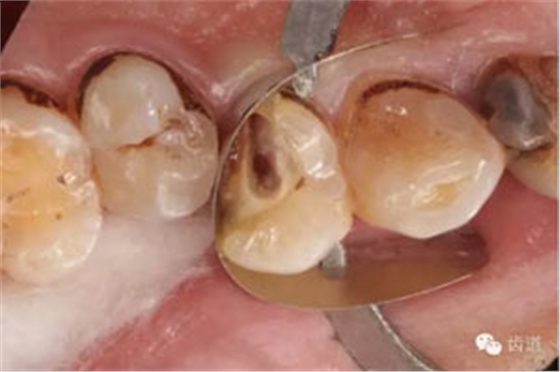

檢查:14遠(yuǎn)中鄰頜面探及齲壞至牙本質(zhì)深層,穿髓。探-,冷-,叩-。松動(dòng)-。牙齦無(wú)紅腫,未探及牙周袋。

數(shù)碼攝影x片顯示:14遠(yuǎn)中鄰頜面暗影,穿髓。根尖暗影。無(wú)牙周膜增寬。

處理:去齲,擴(kuò)大穿髓孔,揭髓室頂,根管探查,探及頰腭兩根管口,去除牙本質(zhì)肩領(lǐng),根管疏通:kfile10#至15#。確定wl。鎳鈦器械MTwo根管預(yù)備至2506。根管預(yù)備中大量使用1%次氯酸鈉和17%edta溶液。預(yù)備結(jié)束后生理鹽水結(jié)合超聲蕩洗,干燥根管,根管內(nèi)放置氫氧化鈣糊劑,Zoe暫封。